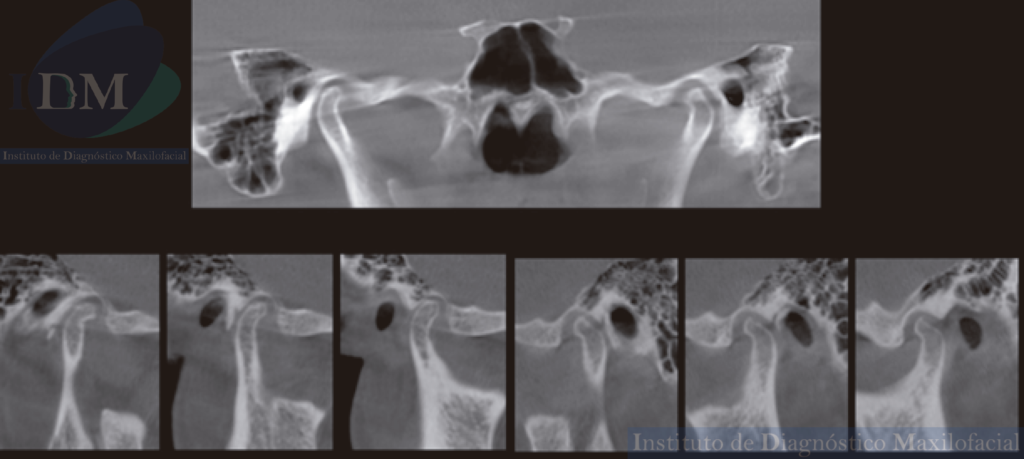

Al observar la tomografía volumétrica de haz cónico (en las reconstrucciones multiplanares, vistas transaxiales y tangenciales) se evidencia la misma imagen de forma redondeada y de densidad ósea que se localiza en la zona infratemporal y en la región posterior del arco cigomático izquierdo próximo a la cavidad glenoidea que a su vez estaría ocasionando un aplanamiento del contorno condilar en su cara externa.

ATM BOCA CERRADA

CORTES SAGITALES